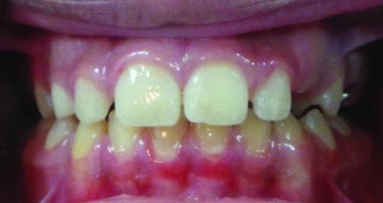

An eight and half year-old girl (LT) attended the paediatric dentistry department of Hamdan Bin Mohammed College of Dental Medicine (HBMCDM) in Dubai Healthcare City for an opinion. The patient’s mother was concerned about the delayed eruption of an upper front tooth (21) that was affecting her child’s appearance (Figs. 1 a, b & c). LT was medically fit and healthy with no history of previous dental trauma. She was in the mixed dentition stage. Tooth 11 had erupted 4 months ago in cross bite but 21 had not erupted yet. Its eruption was much delayed (usually erupts at 7 ½ years of age). Looking back at previous x-rays, a DPT was taken a year ago and it was noticed that an important feature was missed. Retrospectively, the presence of a supernumerary tooth ($) in the area of 21 and congenital missing 47 was confirmed (Fig. 2). Two new x-rays, namely upper intra oral periapicals and the parallax technique (distal shift) showed a supernumerary tooth (conical and inverted) in a palatal position (Figs. 3 a & b). LT also had dental caries of her primary teeth (Figs. 4 a & b), had a pronounced gag reflex and was dentally anxious.

Figs. 1 (a, b & c). An 8 ½ year old girl presented with delayed eruption of 21 and a palpable palatal swelling. Lower teeth were carious; see bitewings in Figure 4